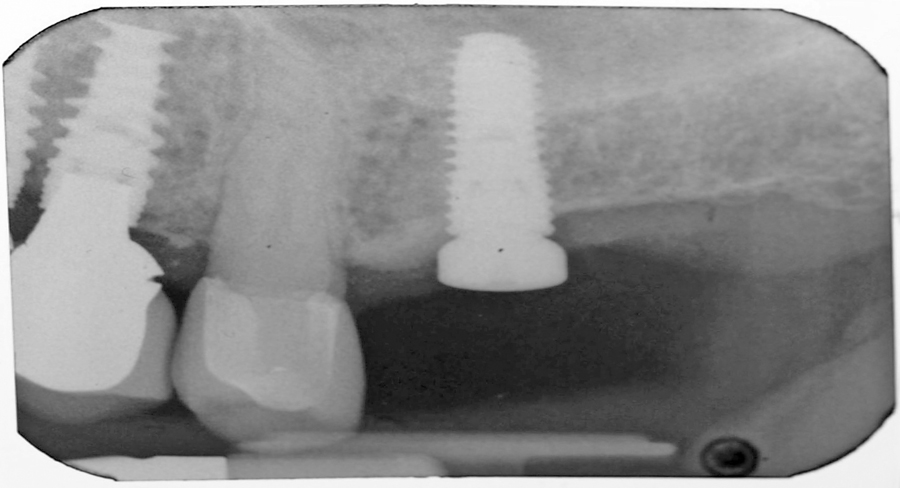

Mrs. Jones and her husband presented to my Prosthodontic Specialty clinic for an additional opinion regarding her treatment options to improve her existing oral condition. After conducting an interview with Mrs. Jones and completing a comprehensive clinical examination, along with diagnostic records, I presented three potential treatment plans. The advantages and disadvantages, risks and benefits … Read more